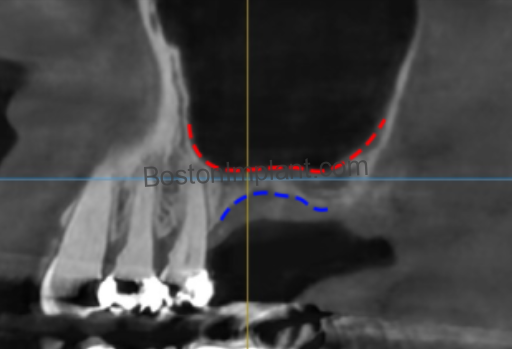

The lateral wall of the sinus contains small blood vessels that must be navigated carefully during the creation of the surgical window.

- The Risk: Approximately 10% of patients have larger vessels in this area that could cause significant bleeding if not identified during planning.

- Prevention & Clinical Protocol: Through “Vessel Mapping” via 3D CBCT imaging, Dr. Lee identifies the exact location of these vessels and plans the surgical access to bypass them entirely.